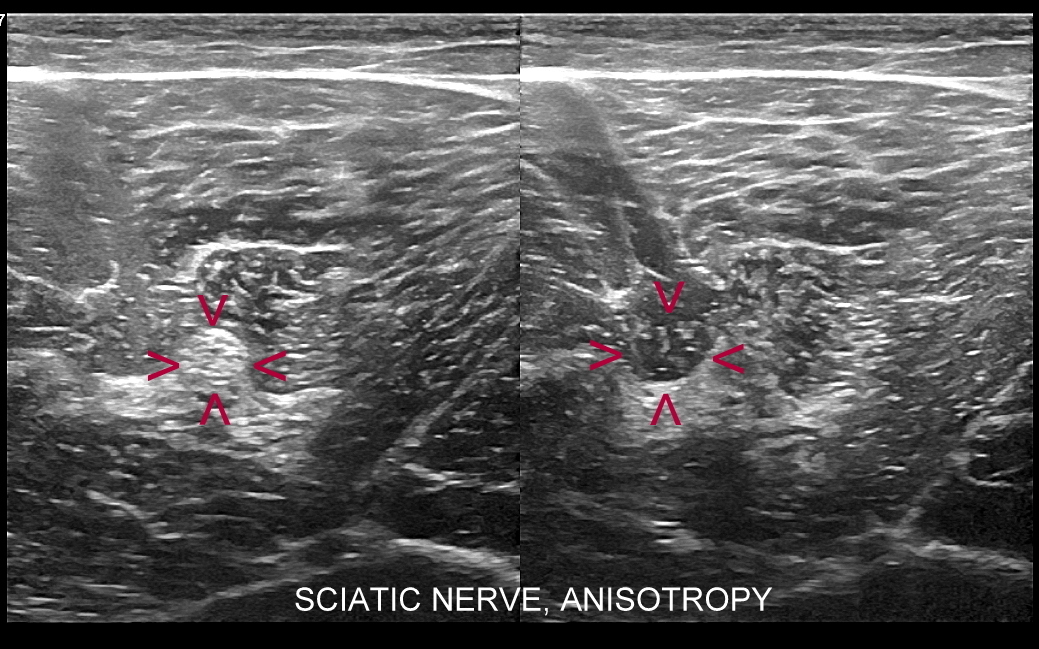

USG nerwów i splotu barkowego

Badanie USG nerwów zostało wprowadzone we Wrocławiu do powszechnego, ambulatoryjnego użycia przez dr Tomasza Szczepańskiego od 2011 roku wraz z powstaniem Interdyscyplinarnej Pracowni USG pierwotnie w Centrum Medycznym Golden Care ®. W zakresie obręczy barkowej i kończyny górnej badanie USG nerwów najczęściej dotyczy splotu barkowego, nerwu pośrodkowego, nerwu łokciowego i nerwu promieniowego. W obrębie kończyny dolnej z kolei zwykle dotyczy nerwu kulszowego i jego gałęzi, tj. nerwu piszczelowego oraz strzałkowego, nerwu skórnego uda bocznego i nerwów skórnych podudzia. Patologie dotyczące nerwów oceniane w USG zwykle obejmują urazy, usidlenia (ang. entrapment) oraz nowotwory nerwów.